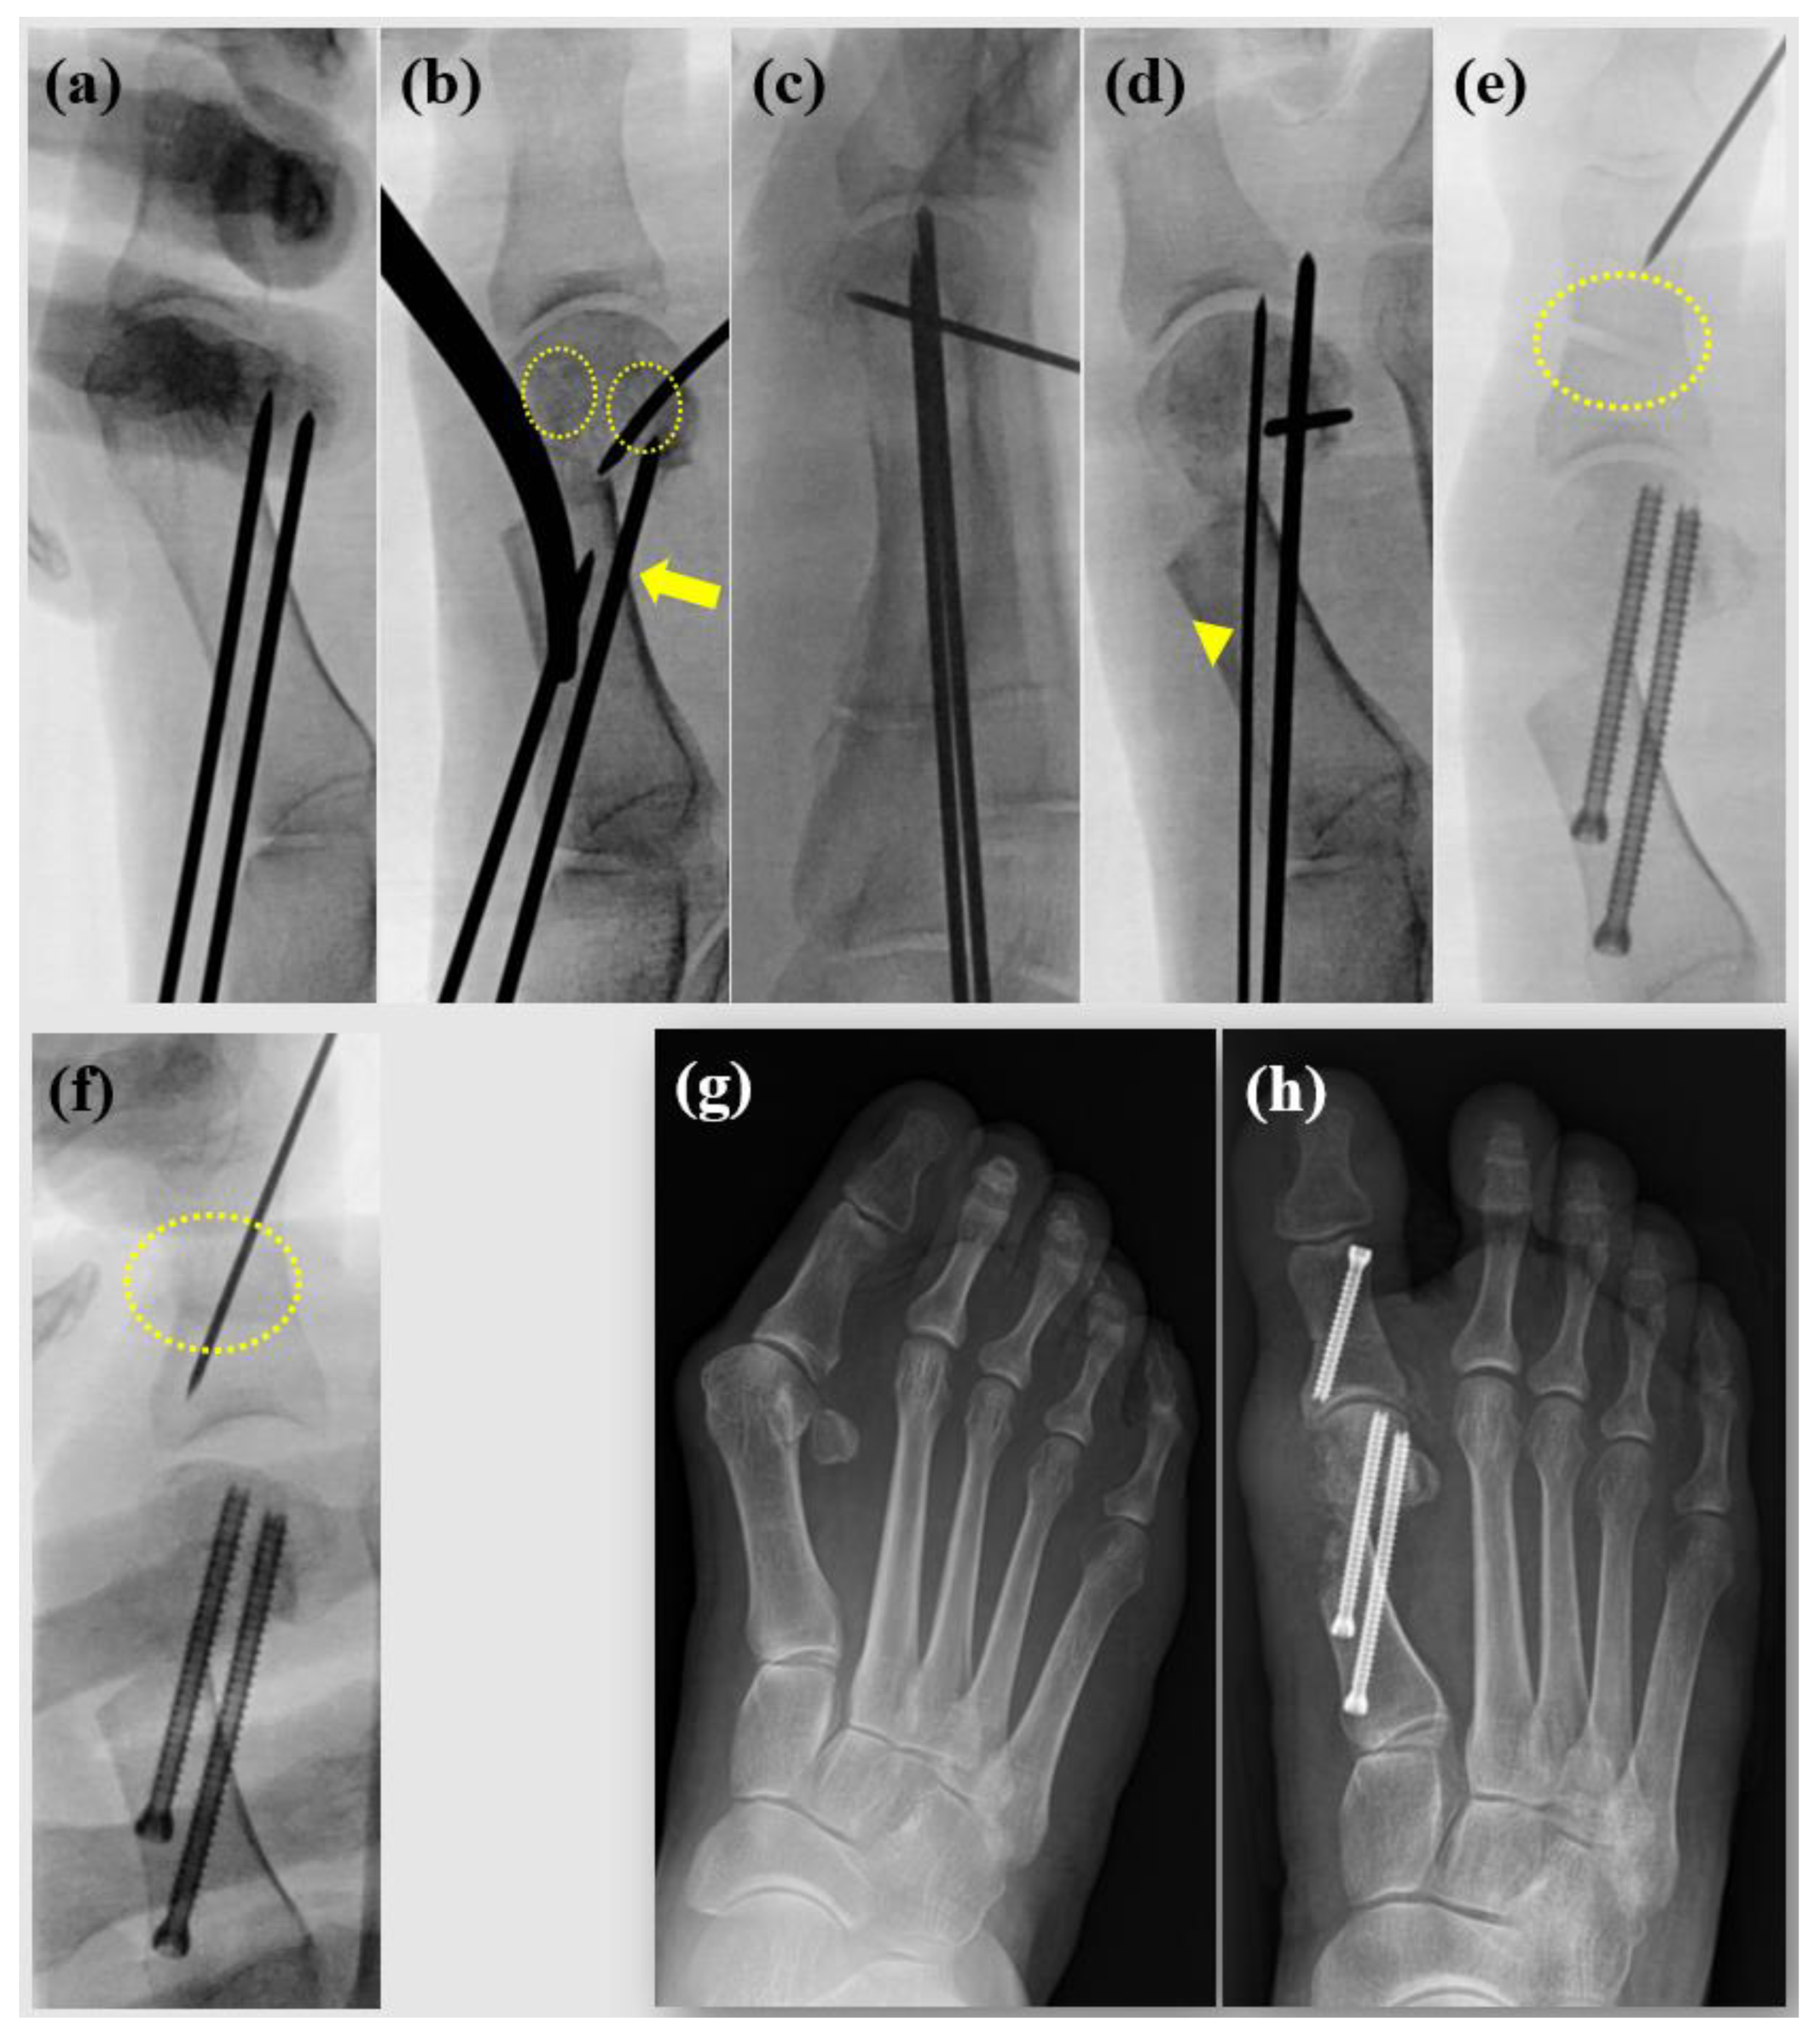

First, a 2.0 mm Kirschner wire (K-wire) is used to predefine the trajectory for fixation screws. This step ensures an optimal direction for screw insertion after the osteotomy (Figure 1a). The pre-inserted K-wires are then partially withdrawn proximally beyond the planned osteotomy site. A small incision (~3 mm) is made just proximal to the sesamoid complex. To prevent 1st metatarsal shortening caused by the burr thickness and lateral shift of the 1st metatarsal, a perpendicular osteotomy is performed on the 1st metatarsal using a Midas Rex® Legend® burr (Medtronic, Dublin, Ireland). The burr speed is set to 8000 rpm, and constant irrigation using a syringe is maintained to prevent thermal burns. Once the osteotomy is complete, a large Kelly forceps is used to translate the distal osteotomy fragment laterally. A 1.6 mm K-wire is inserted into the metatarsal head to stabilize the fragment, which is supinated to correct pronation deformity and achieve sesamoid reduction (dotted circles, Figure 1b). It is ensured that the proximal K-wire securely purchases the lateral cortex of the proximal segment (arrow). If a DMAA correction is required, the K-wire may be adjusted and used as a joystick to fine-tune alignment. Once the distal fragment is translated to the desired position, the pre-inserted 2.0 mm K-wire is reinserted to fix the osteotomy temporarily. In the figure-of—4 position, the foot’s lateral view is checked to confirm the absence of sagittal plane deformities (Figure 1c). After verifying the proper positioning and fixation of the distal fragment and K-wires, the distal 2.0 mm K-wire is replaced with a guide wire manually for screw insertion (Figure 1d). Drilling is performed, and a cannulated screw system (Jeil Medical Corporation, Seoul, Korea) is used to fixation. The same technique is applied for the proximal screw fixation, completing the stabilization process. If MTP joint incongruency is observed, a beaver knife is used to release the adductor tendon, lateral MTP joint capsule, and lateral metatarso-sesamoid ligament. The hallux is gently overcorrected to ensure adequate release of the lateral joint space. If necessary, an Akin osteotomy is performed using the Midas burr. Care is taken to preserve enough of a portion of the lateral cortex of the proximal phalanx. Fluoroscopy confirms a precise medial closing wedge osteotomy before inserting guide wire for screw fixation (dotted circles, Figure 1e,f). Pre- and postoperative radiographs are shown (Figure 1g,h).

Figure 1. Surgical procedures. (a) Pre K-wiring for ideal screw positioning before osteotomy. (b) Sesamoid reduction with metatarsal head rotation (dotted circles), purchasing lateral cortex of proximal metatarsal (arrow). (c) Check lateral image to confirm proper sagittal alignment. (d) K-wires are exchanged manually to guide wire for screw insertion (arrowhead). (e) During Akin osteotomy procedure, ensuring that the lateral cortex is preserved and is advantageous for precise medial closing, (f) ensure that the medial closing is precisely achieved before inserting the guide pin. (g) Preoperative radiograph. (h) Postoperative radiograph.